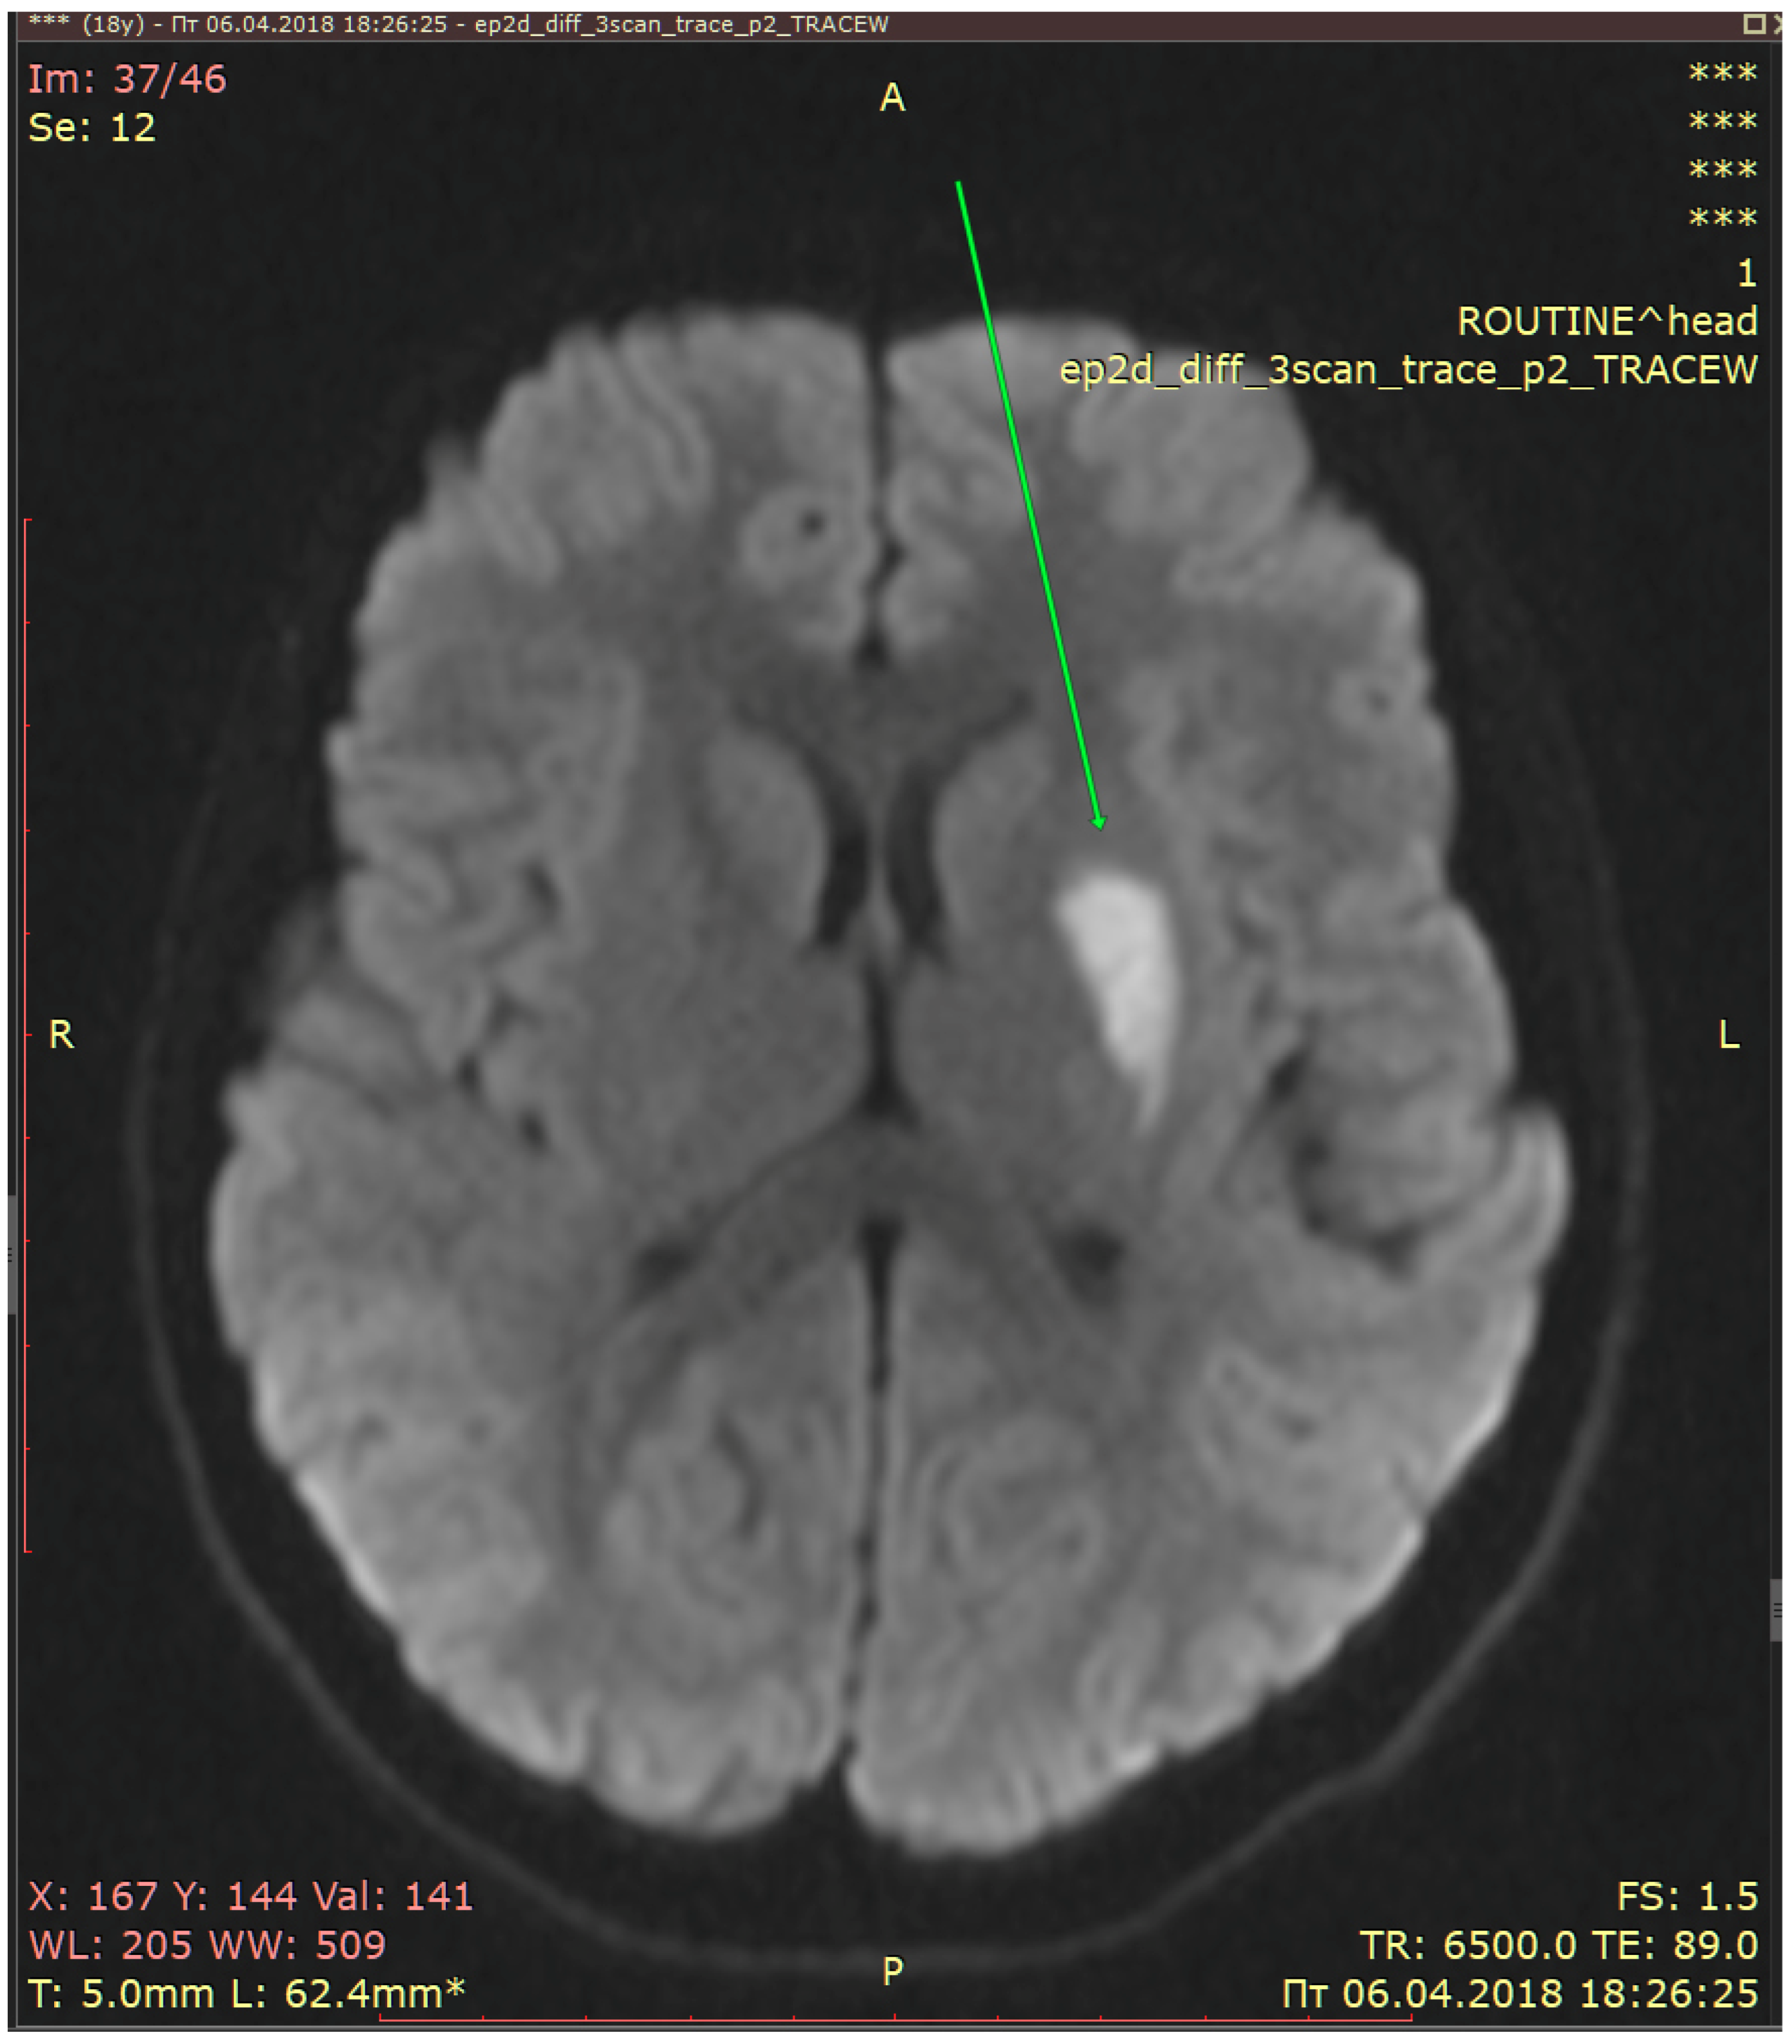

2.3. Diagnostic Assessment and Evaluation